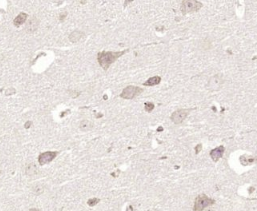

多聚甲醛固定,石蜡包埋(小鼠脑组织);用柠檬酸钠缓冲液(pH6.0)煮沸15min后获得抗原;用3%过氧化氢阻断内源性过氧化物酶20分钟;阻断缓冲液(正常山羊血清)在37℃下30min;用BMPER聚合酶进行抗体孵育。未结合的克隆抗体在1:400下在4°C下过夜,然后根据SP试剂盒(兔子)说明和DAB染色进行操作。